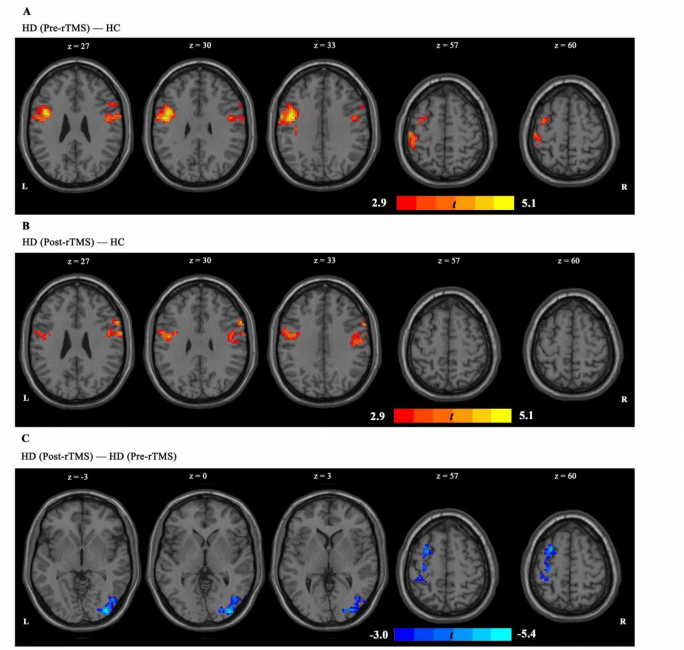

上图为经颅磁刺激后左侧 IPL 与全脑网络之间的功能连接,采用双样本t检验。A图显示,与 HC组相比,HD(治疗前)组左侧IPL-左中央前回偶联和左侧IPL-右额下回耦联增加。B图显示,经rTMS治疗后,HD组左IPL-左中央前回耦联和左IPL-右额下回耦联异常增加明显减少,在完成 7 个疗程的 rTMS 治疗后,呈接近HC组的趋势。C图显示 rTMS 对左侧IPL-左侧额中回偶联和左侧IPL-右侧枕下回耦联有显著影响。在这两个区域,经过 7 次经颅磁刺激疗程后,功能连通性显著下降。

上图为经颅磁刺激后右侧 IPL 与全脑网络之间的功能连接。

A图显示,HD组(治疗前)的右侧 IPL-左侧中央前回偶联和右侧 IPL-右侧中央前回偶联均有所增加。B图显示,在 7 个疗程的经颅磁刺激后,这些异常增加的连接减少了